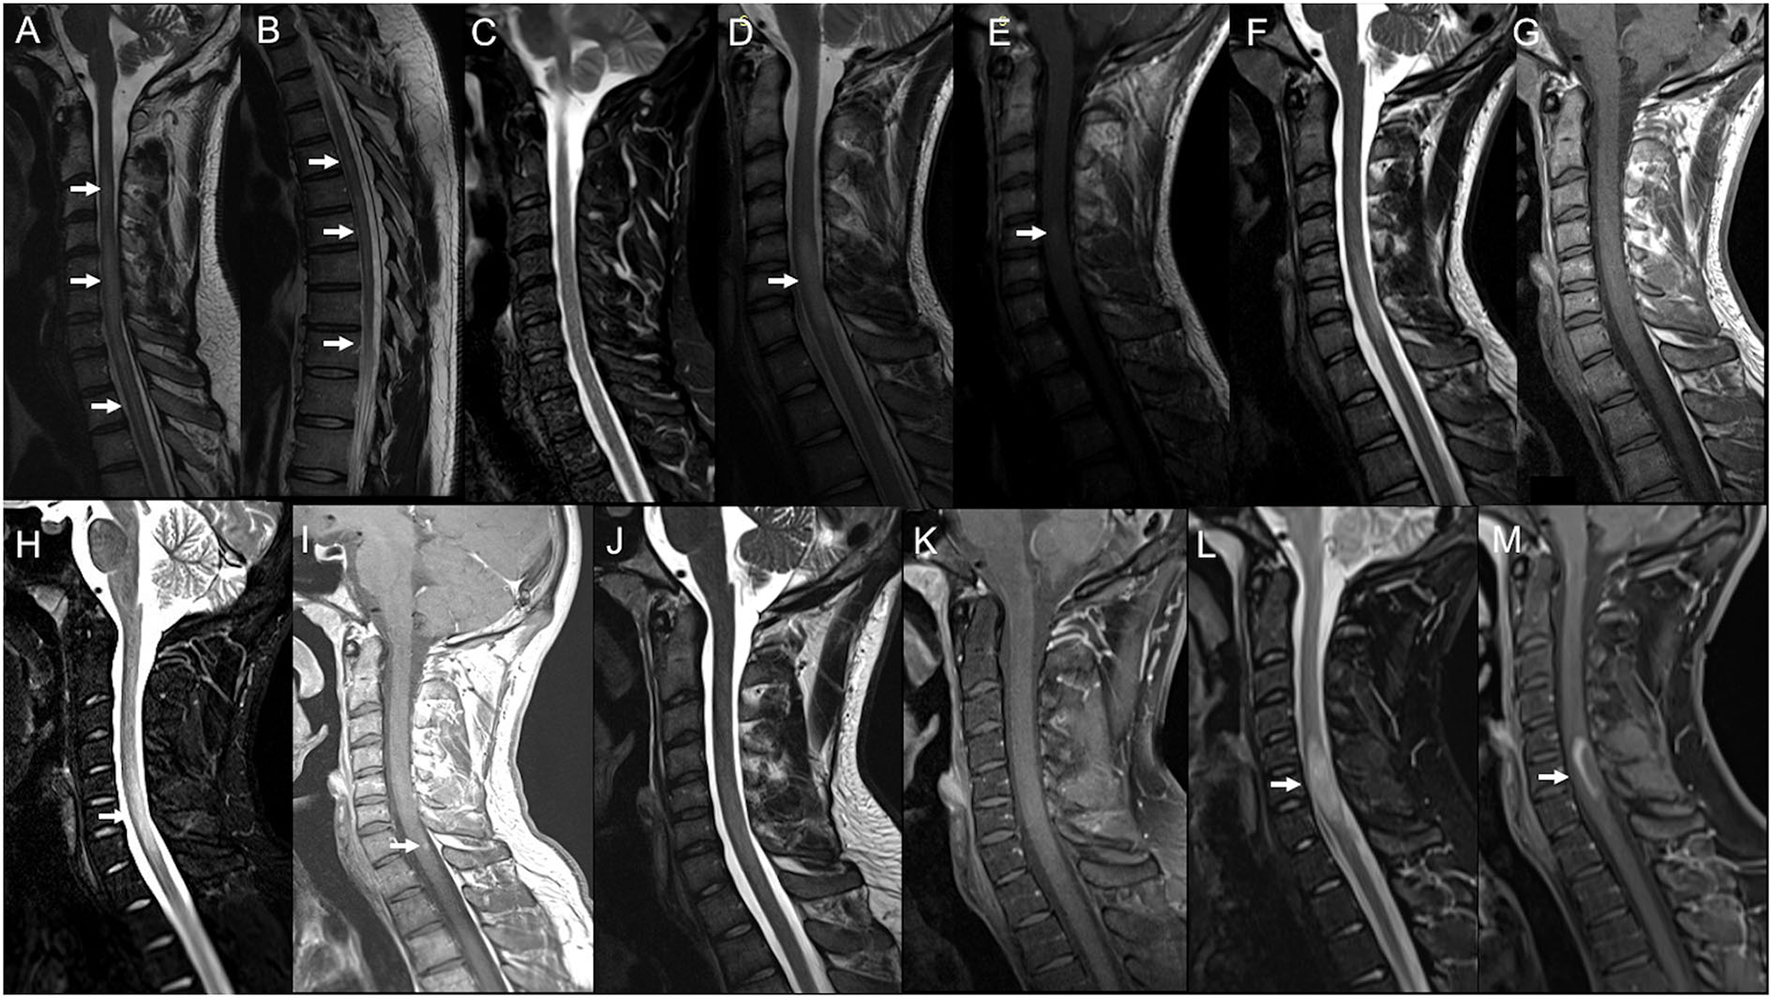

Figure 1

Serial spinal cord MRI scans in Case 1 (A–C) and Case 2 (D–M). Case 1: Cervical (A) and thoracic (B) spinal cord MRI obtained 10 days after Ad26.COV2.S first dose showed a T2-weighted hyperintensity irregularly extending from C3 to medullaris conus with swelling from C4 to C7 (arrows) and no gadolinium enhancement (not shown). (C) 8-months MRI follow-up showing the complete resolution of the swelling and marked amelioration of the signal abnormality, barely visible on Short Tau Inversion Recovery (STIR) images. Case 2: (D) Spinal cord MRI performed 3 months after Tdap and IVP vaccine administration, showing a T2-weighted hyperintensity from C5 to C7 (arrow) with swelling and blurred contrast-enhancement on T1-weighted sequence (E) (arrow). (F) 6-months MRI control showing the cervical lesion shrinkage on T2-weighted sequences and no more contrast-enhancement (G). (H) Spinal cord MRI obtained 8 days after the BNT162b2 second dose, showing swelling on STIR (arrow) and gadolinium enhancement [(I); arrow] of the previously detected lesion. (J) 4-months MRI showed showing marked reduction of the signal abnormality and no more enhancement on the T1-weighted image (K). (L) Spinal cord MRI obtained 62 days after the BNT162b2 third dose, showing a new swelling (arrow) and gadolinium ring enhancement (M) of the known cervical lesion.

A 34-year-old man, with unremarkable past medical history, presented with numbness in his arms 8 days after receiving the first dose of Ad26.COV2.S vaccine. His condition worsened in a few days: numbness extended to his trunk and legs, and he progressively developed lower limb weakness and urinary retention. He entered our unit 4 days later. On neurological exam, he had light touch/pin-prick hypoesthesia below C4 level, four limbs weakness, and sphincter disturbances requiring catheterization. A spinal cord MRI showed a T2-weighted hyperintensity irregularly extending from C3 to medullaris conus (appearing swallowing from C4 to C7) with no gadolinium enhancement on T1-weighted images (Figures 1A,B); brain MRI resulted negative. Blood count, erythrocyte sedimentation rate, and C-reactive protein were normal. Cerebrospinal fluid (CSF) analysis revealed marked lymphocytosis (310 leucocytes, 90% mononuclear cells) and a slightly elevated protein level. No infectious agent was detected at CSF PCR testing for extensive infectious panel (Herpesviruses, Enterovirus, Parechovirus, i K1, Haemophilus influenzae, Listeria monocytogenes, Neisseria meningitidis, Streptococcus agalactiae, Streptococcus pneumoniae, and Cryptococcus neoformans/gattii). CSF immunoelectrophoresis (IEP) showed no oligoclonal bands (OCB). Serum anti-AQP-4 and anti-MOG antibodies were negative, as well as an antibody panel for connective tissue diseases. The patient was administered a 5-day course of high-dose IV methylprednisolone (IVMP) followed by oral tapering. After 2 weeks, he showed an almost complete motor recovery in the arms while lower limb weakness and sphincter disturbances partially improved. He started rehabilitation treatment and after 4 months he reported marked amelioration of leg strength and further recovery of limb hypoesthesia. At 8 months of control, he remained clinically stable and MRI showed the complete resolution of the cervical swelling, with the extended T2-hyperintensity appearing fragmented in multiple shorter lesions, barely visible (Figure 1C); brain MRI was still negative.

A 19-year-old man with a negative past medical history presented with numbness and weakness in his right arm in December 2018, 3 months after receiving Diphtheria/Tetanus/Pertussis (Tdap) and Poliovirus (IVP) vaccine booster doses. Symptoms spontaneously resolved in 2 weeks. Three months later, he underwent a spinal cord MRI showing a T2-weighted hyperintensity from C5 to C7, with swelling and blurred contrast-enhancement (Figures 1D,E); the brain MRI was negative. CSF analysis revealed normal cell count/protein level and IEP showed the presence of three OCBs (pattern II, OCB exclusively in CSF). CSF PCR testing for the extensive infectious panel was positive for Enterovirus, but this result was not considered significant due to the absence of prodromal respiratory/gastroenteric illness and clinical/MRI/CSF findings not suggestive of Enterovirus-related ATM. Serum antibodies panel for infectious diseases (including HIV, Herpesviruses, and Borrelia) was unremarkable as well as anti-AQP-4/MOG and connective tissue diseases antibodies. At 6-months of MRI control the cervical lesion appeared shrunk in volume, with no more contrast-enhancing, and no other lesions were detected in the spinal cord and brain (Figures 1F,G). He remained stable at clinical and radiological follow-ups for the next two years, with the last MRI performed in February 2021. On 3rd June 2021, he received the first dose of the BNT162b2 vaccine and the second dose on 28th June. After 8 days, he underwent a brain and spinal cord MRI follow-up, showing the swelling and gadolinium enhancement of the previously detected cervical lesion (Figures 1H,I). He did not complain of any symptoms, except for a mild right-hand numbness occurring 3 weeks after the second dose and lasting for a few days. At a brain and spinal cord MRI performed 4 months later, the cervical lesion appeared reduced in dimension and did not show enhancement (Figures 1J,K). On 22nd December 2021, the patient received the third dose of BNT162b2. After 35 days, he reported numbness in his right arm followed by his right limb weakness. He was admitted to our neurology unit and a new spinal cord MRI showed the swelling and contrast enhancement of the pre-existing cervical lesion (Figures 1L,M); the brain MRI was still negative. A new lumbar puncture showed normal cell count/protein level with no infectious agent detected at PCR, while IEP revealed again the presence of three OCBs (pattern II). Serum anti-AQP-4/anti-MOG and antibodies panel for connective tissue diseases were still unremarkable. The patient was administrated a 5-day course of high-dose IVMP followed by Oral Corticosteroid (OCS) tapering, showing complete recovery after a week. At 4-months of control, he was clinically stable and did not report relapses. He is currently under clinical/radiological follow-up.